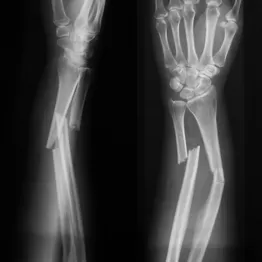

着想はなんと海のカキ。岩や橋脚に強固にくっつく際の接着タンパク質を模倣し、人体天然成分を合成した。従来の金属プレートやスクリューによる固定は不要で、骨の自然治癒過程で接着剤自体が半年以内に体内に吸収されるため、再手術もしなくて済む。ある手首の粉砕骨折患者の場合、2~3センチの切開で3分以内に固定され、3カ月後には完全に機能を回復。感染や合併症もなかった。